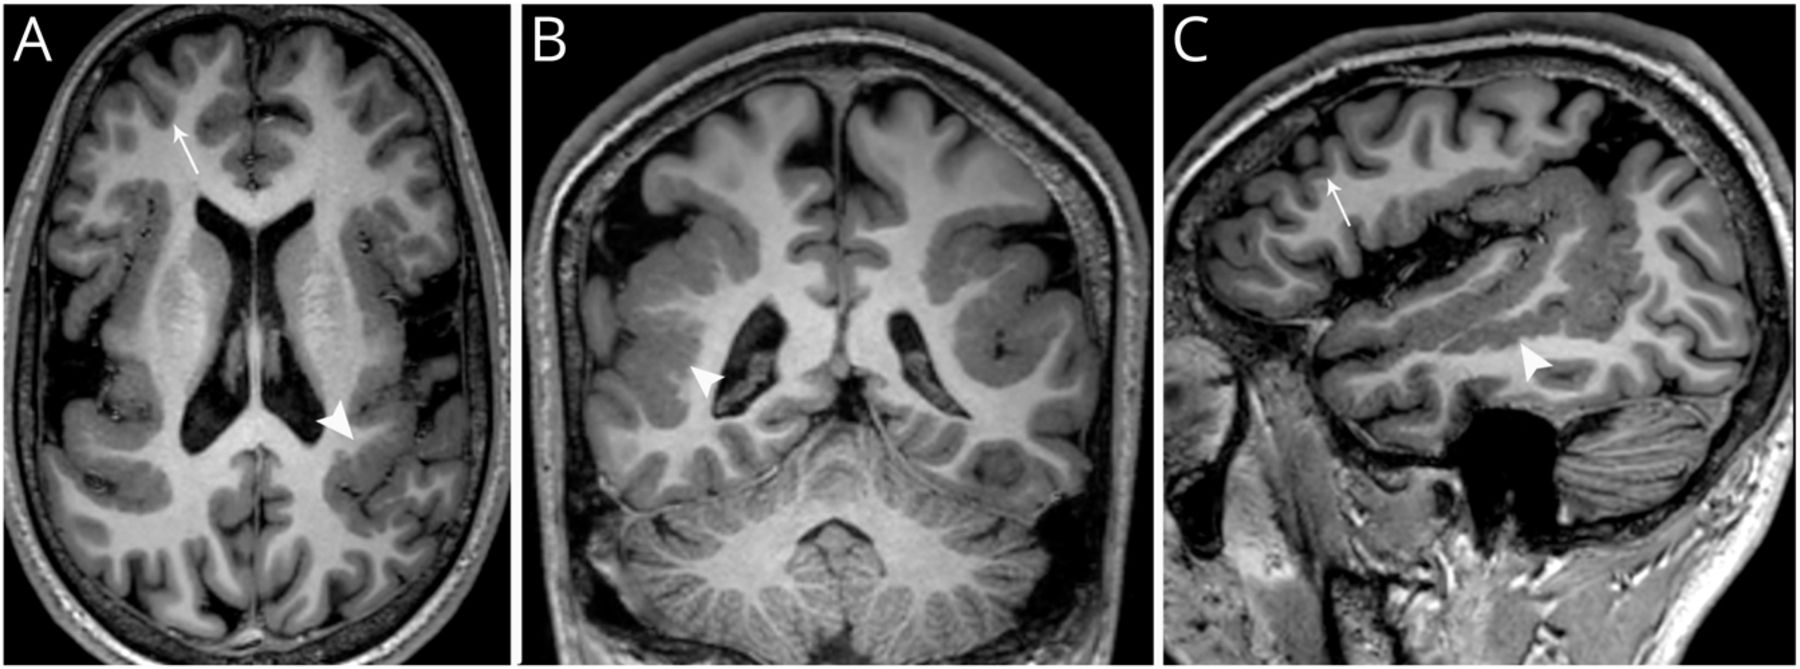

一个15岁的男孩提出了5年顽固性局灶性癫痫发作,每天4-6次。癫痫发作的符号学描述为左半边身体麻木,接着是强直姿势和头部向左移动,并持续30秒的意识丧失。其他症状包括认知障碍,言语迟缓和言语困难。神经心理学评估显示智力和认知能力受损。脑部MRI显示双侧左半球多小回症(图中,得了)。BPP是一种皮质发育畸形1特点是Sylvian裂缝变宽,异常小的脑回和浅沟数量增加。患者表现为构音障碍和难治性癫痫。2

图1

轴位(A)、冠状面(B)和矢状面(C) t1加权图像显示皮层表面沿双侧侧裂和颞上沟呈波动和不规则

与额极灰质(箭头)相比,多微回皮层明显增厚,灰质交界处(箭头)也可见点状和不规则。